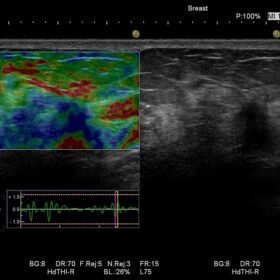

Ultrasound HI VISION Ascendus – Image Gallery and Videos

Radiology 2D, Color, Contrast, Elasto and RVS mode